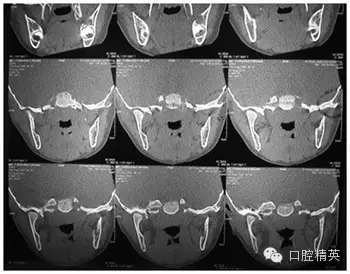

CT

圖